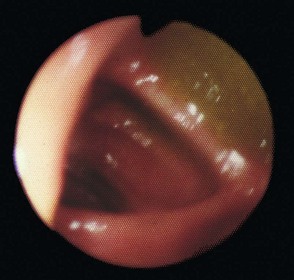

Diagnostic and therapeutic duodenoscopy: A side-viewing duodenoscope can be used to inspect the duodenal papilla and guide insertion of a cannula or therapeutic tools. Cannulation allows injection of contrast material into the common bile duct and separately into the pancreatic duct. The technique is known as ERCP (endoscopic retrograde cholangio-pancreatography) (see Fig. 5.17 and Ch. 11) and is an important part of gastroenterological investigation.